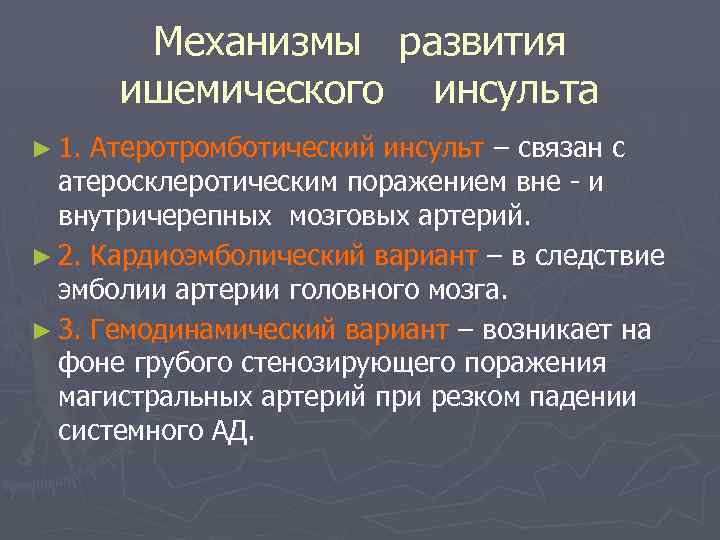

Механизмы развития ишемического инсульта ► 1. Атеротромботический инсульт – связан с атеросклеротическим поражением вне - и внутричерепных мозговых артерий. ► 2. Кардиоэмболический вариант – в следствие эмболии артерии головного мозга. ► 3. Гемодинамический вариант – возникает на фоне грубого стенозирующего поражения магистральных артерий при резком падении системного АД.